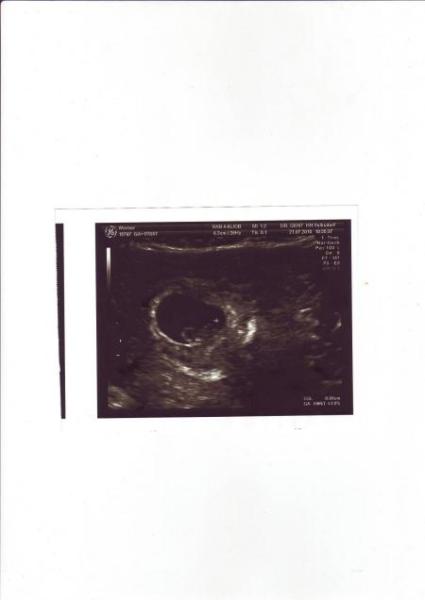

Bin auch wieder da und ganz happy. Alles ist super, alles ist zeitgemäß entwickelt, besser geht es nicht. Meinen MuPa habe ich auch schon bekommen und am 17.08. wird dieses große Screening gemacht, wo es auf Herz und Nieren durchleuchtet wird. Man was bin ich happy. Jetzt freue ich mich wirklich und bin jetzt auch entspannter und genieße es. Hab zur Zeit allerdings starke Übelkeit und ziemliche Kreislaufbeschwerden. Meine Männer sind jetzt am See und ich genieße die Ruhe und werde mich erstmal etwas hinlegen. GlG Claudia